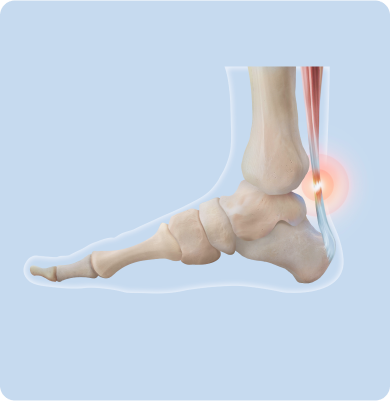

아킬레스건염

종아리 근육과 발꿈치를 연결하는 아킬레스건에 염증이 생기는 질환

주요원인

갑작스러운 운동량 증가, 준비 운동 없이 무리한 활동, 딱딱한 바닥에서의 반복적 충격, 하이힐이나 맞지 않는 신발 착용, 종아리 근육의 유연성 저하 등이 아킬레스건에 반복적인 자극을 주어 발생합니다.

주요증상

• 걷거나 뛸 때, 계단을 오르내릴 때 통증이 심해지고 휴식 시 완화됩니다.

• 아침에 첫 발을 디딜 때 뻣뻣하거나 통증이 느껴집니다.

• 아킬레스건 부위가 붓고 눌렀을 때 통증이 있습니다.